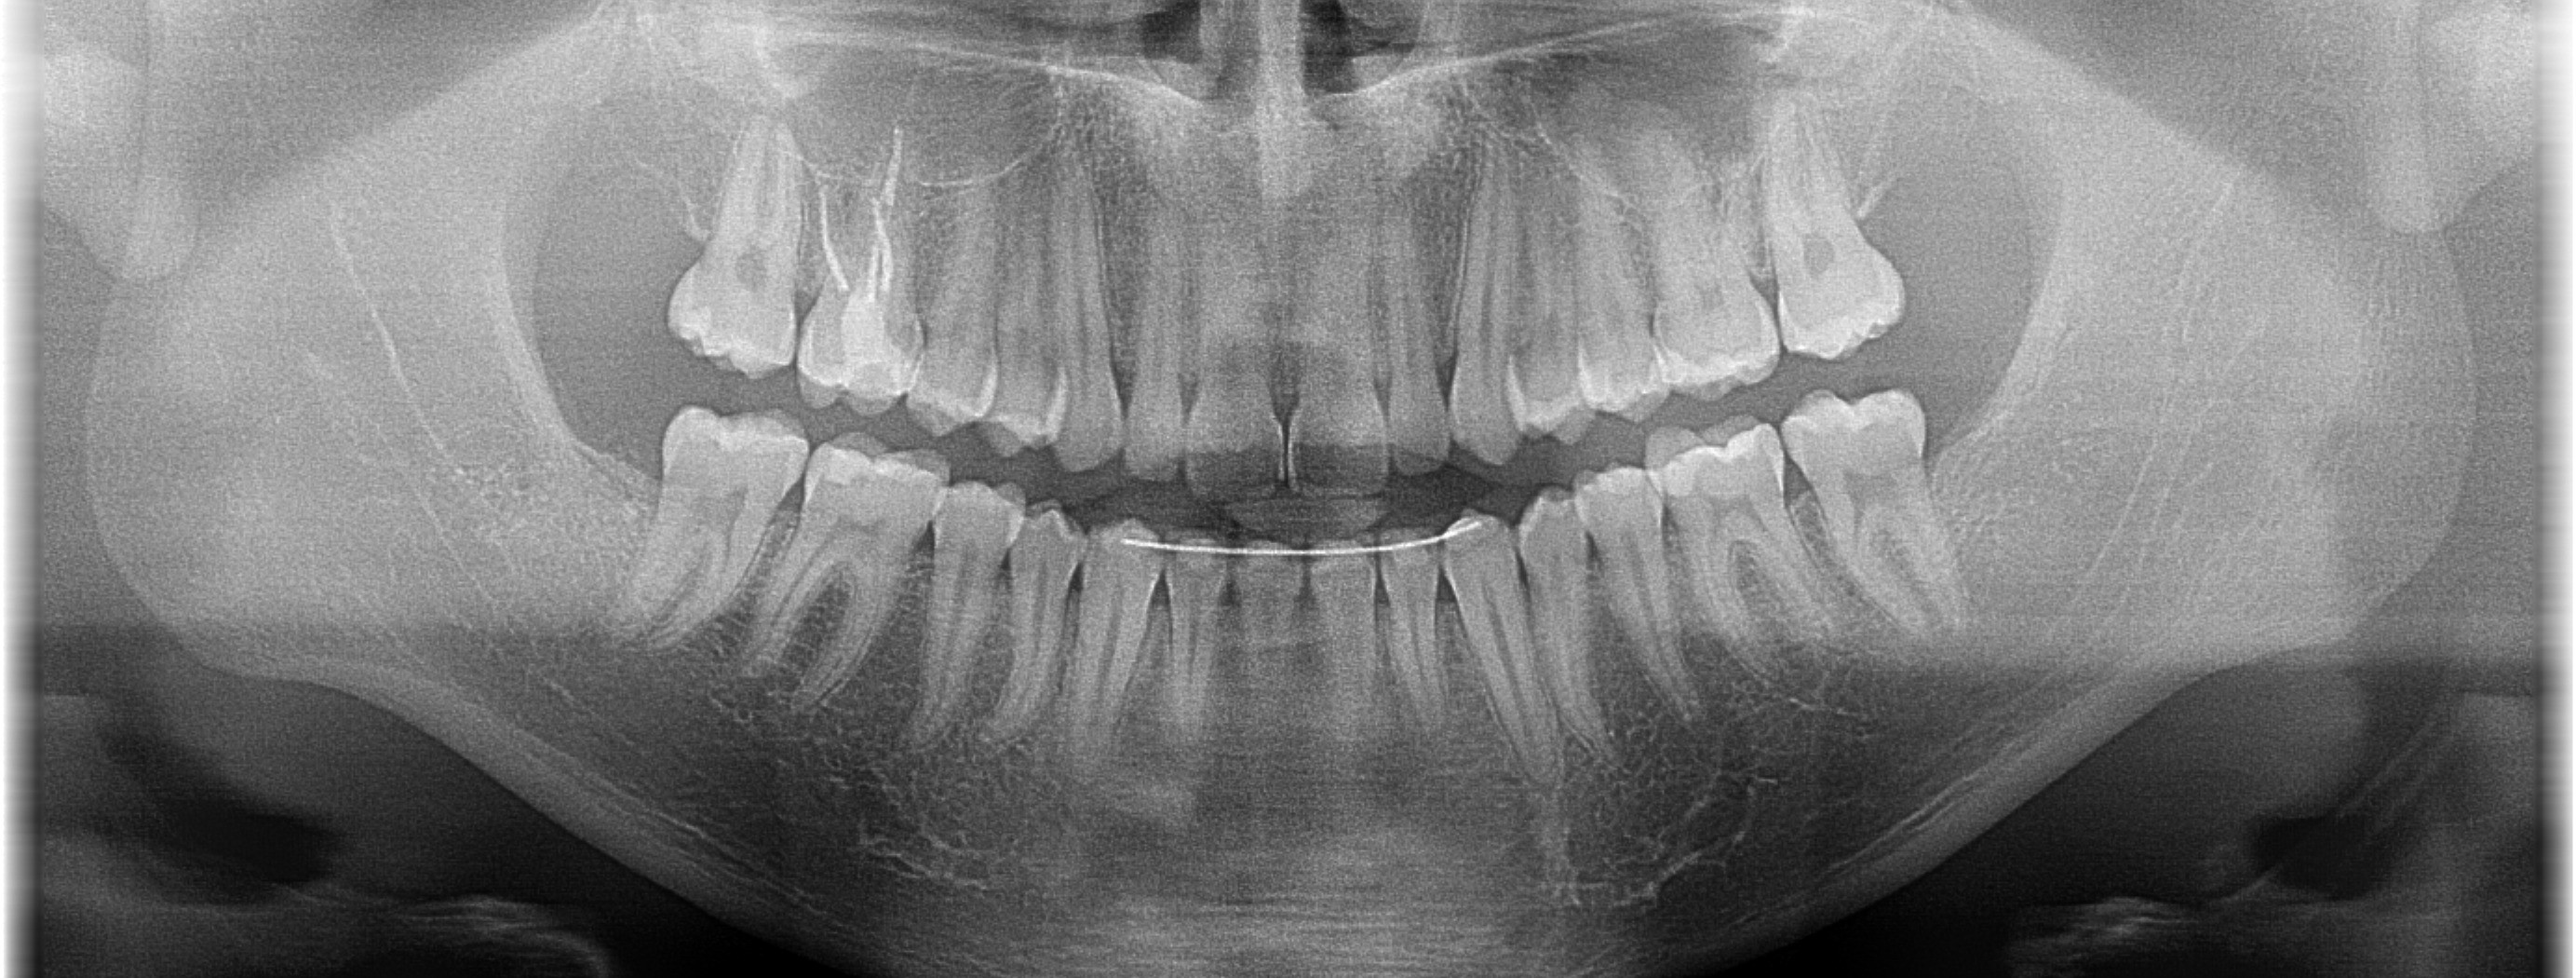

Pan Maciej z Katowic zgłosił się celem usunięcia ósemek zleconym przez lekarza ortodontę po zakończonym leczeniu. Nie usunięte na czas ósemki mogą wyżynając się zniweczyć efekt leczenia ortodontycznego, poprzez przesunięcie ustawionych już w łuku zębów. Zabieg przeprowadzono w narkozie usuwając zatrzymane ósemki minimalnie inwazyjnie tj. atraumatycznie i zaopatrując rany poekstrakcyjne odwirowanym osoczem Pacjenta (PRF). Gojenie przebiegało prawidłowo, bez powikłań i dolegliwości.